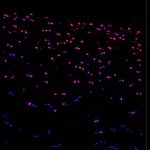

- These are H&E staining and MxIF images from SenNet research & HuBMAP researcher, Dr. Pei-Hsun Wu, at the Wirtz lab at Johns Hopkins University . 4 images of the skin from a human scalp. The pink, purple, and white images on the left are H&E staining, the multicolored ones on the right are multiplex immunofluorescent imaging- blue – nuclei, yellow – cell division, red – epidermal cells, green – cellular aging